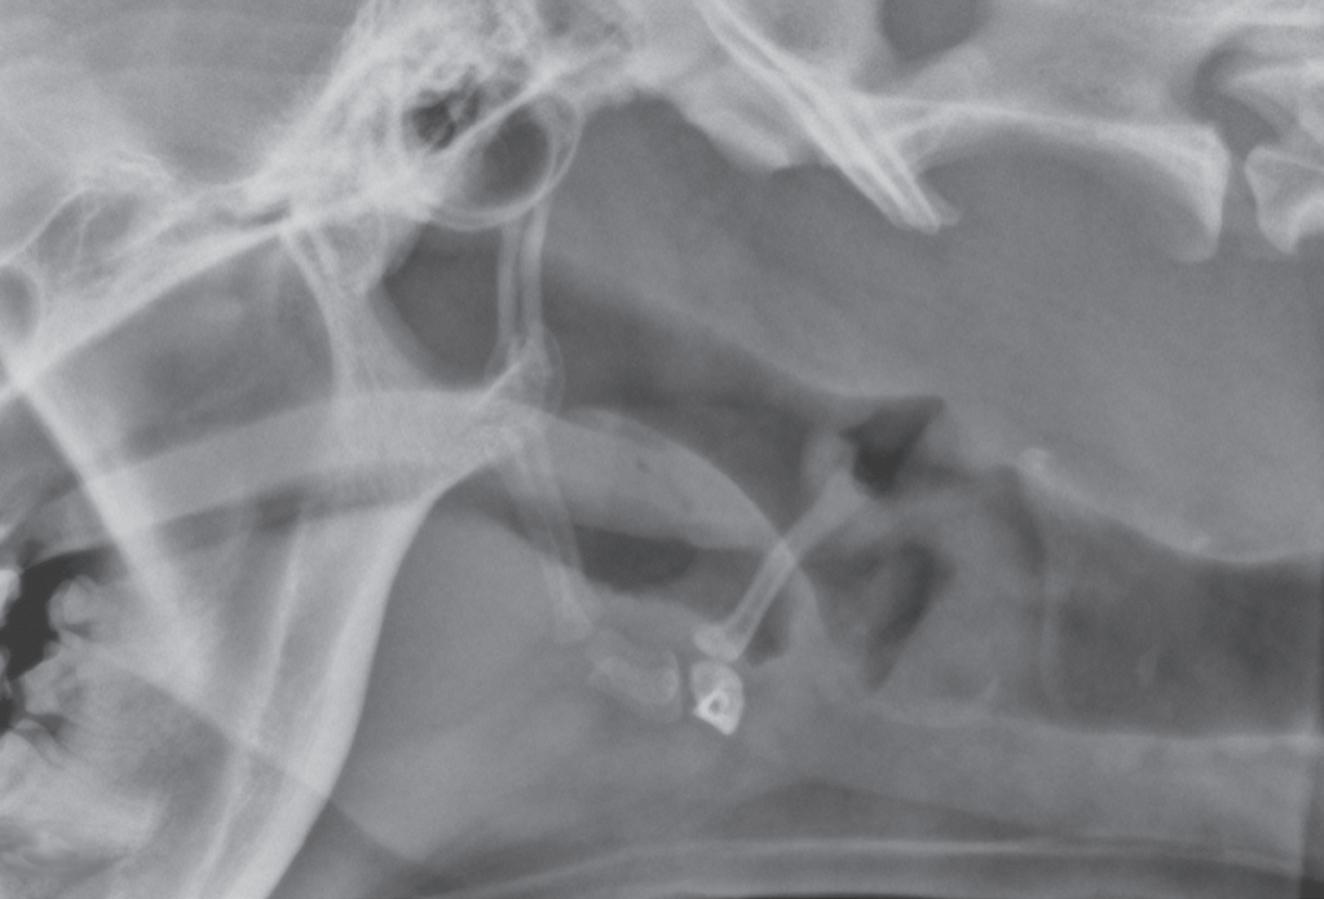

Figure 1-6. Dorsoventral (A), lateral (B), and rostrocaudal (C) radiographs of a box turtle. In A and B, which are orthogonal to each other, it is clear that the subject is a turtle. Eggs are visible in the coelom. In C, which is also an orthogonal view with respect to both A and B, it is not obvious that the subject is a turtle because this orientation is uncommon and unfamiliar. The eggs are also not visible in C.